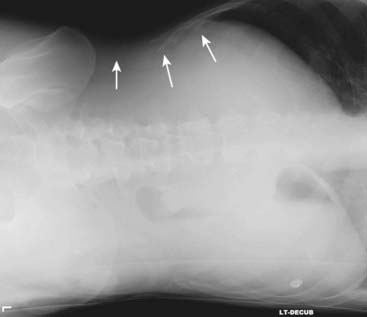

Figure 13-5 Aerophagia.

Virtually all bowel gas comes from swallowed air. Swallowing large quantities of air may produce a picture called aerophagia, characterized by numerous polygonal-shaped, air-containing loops of bowel, none of which is dilated (white circle).